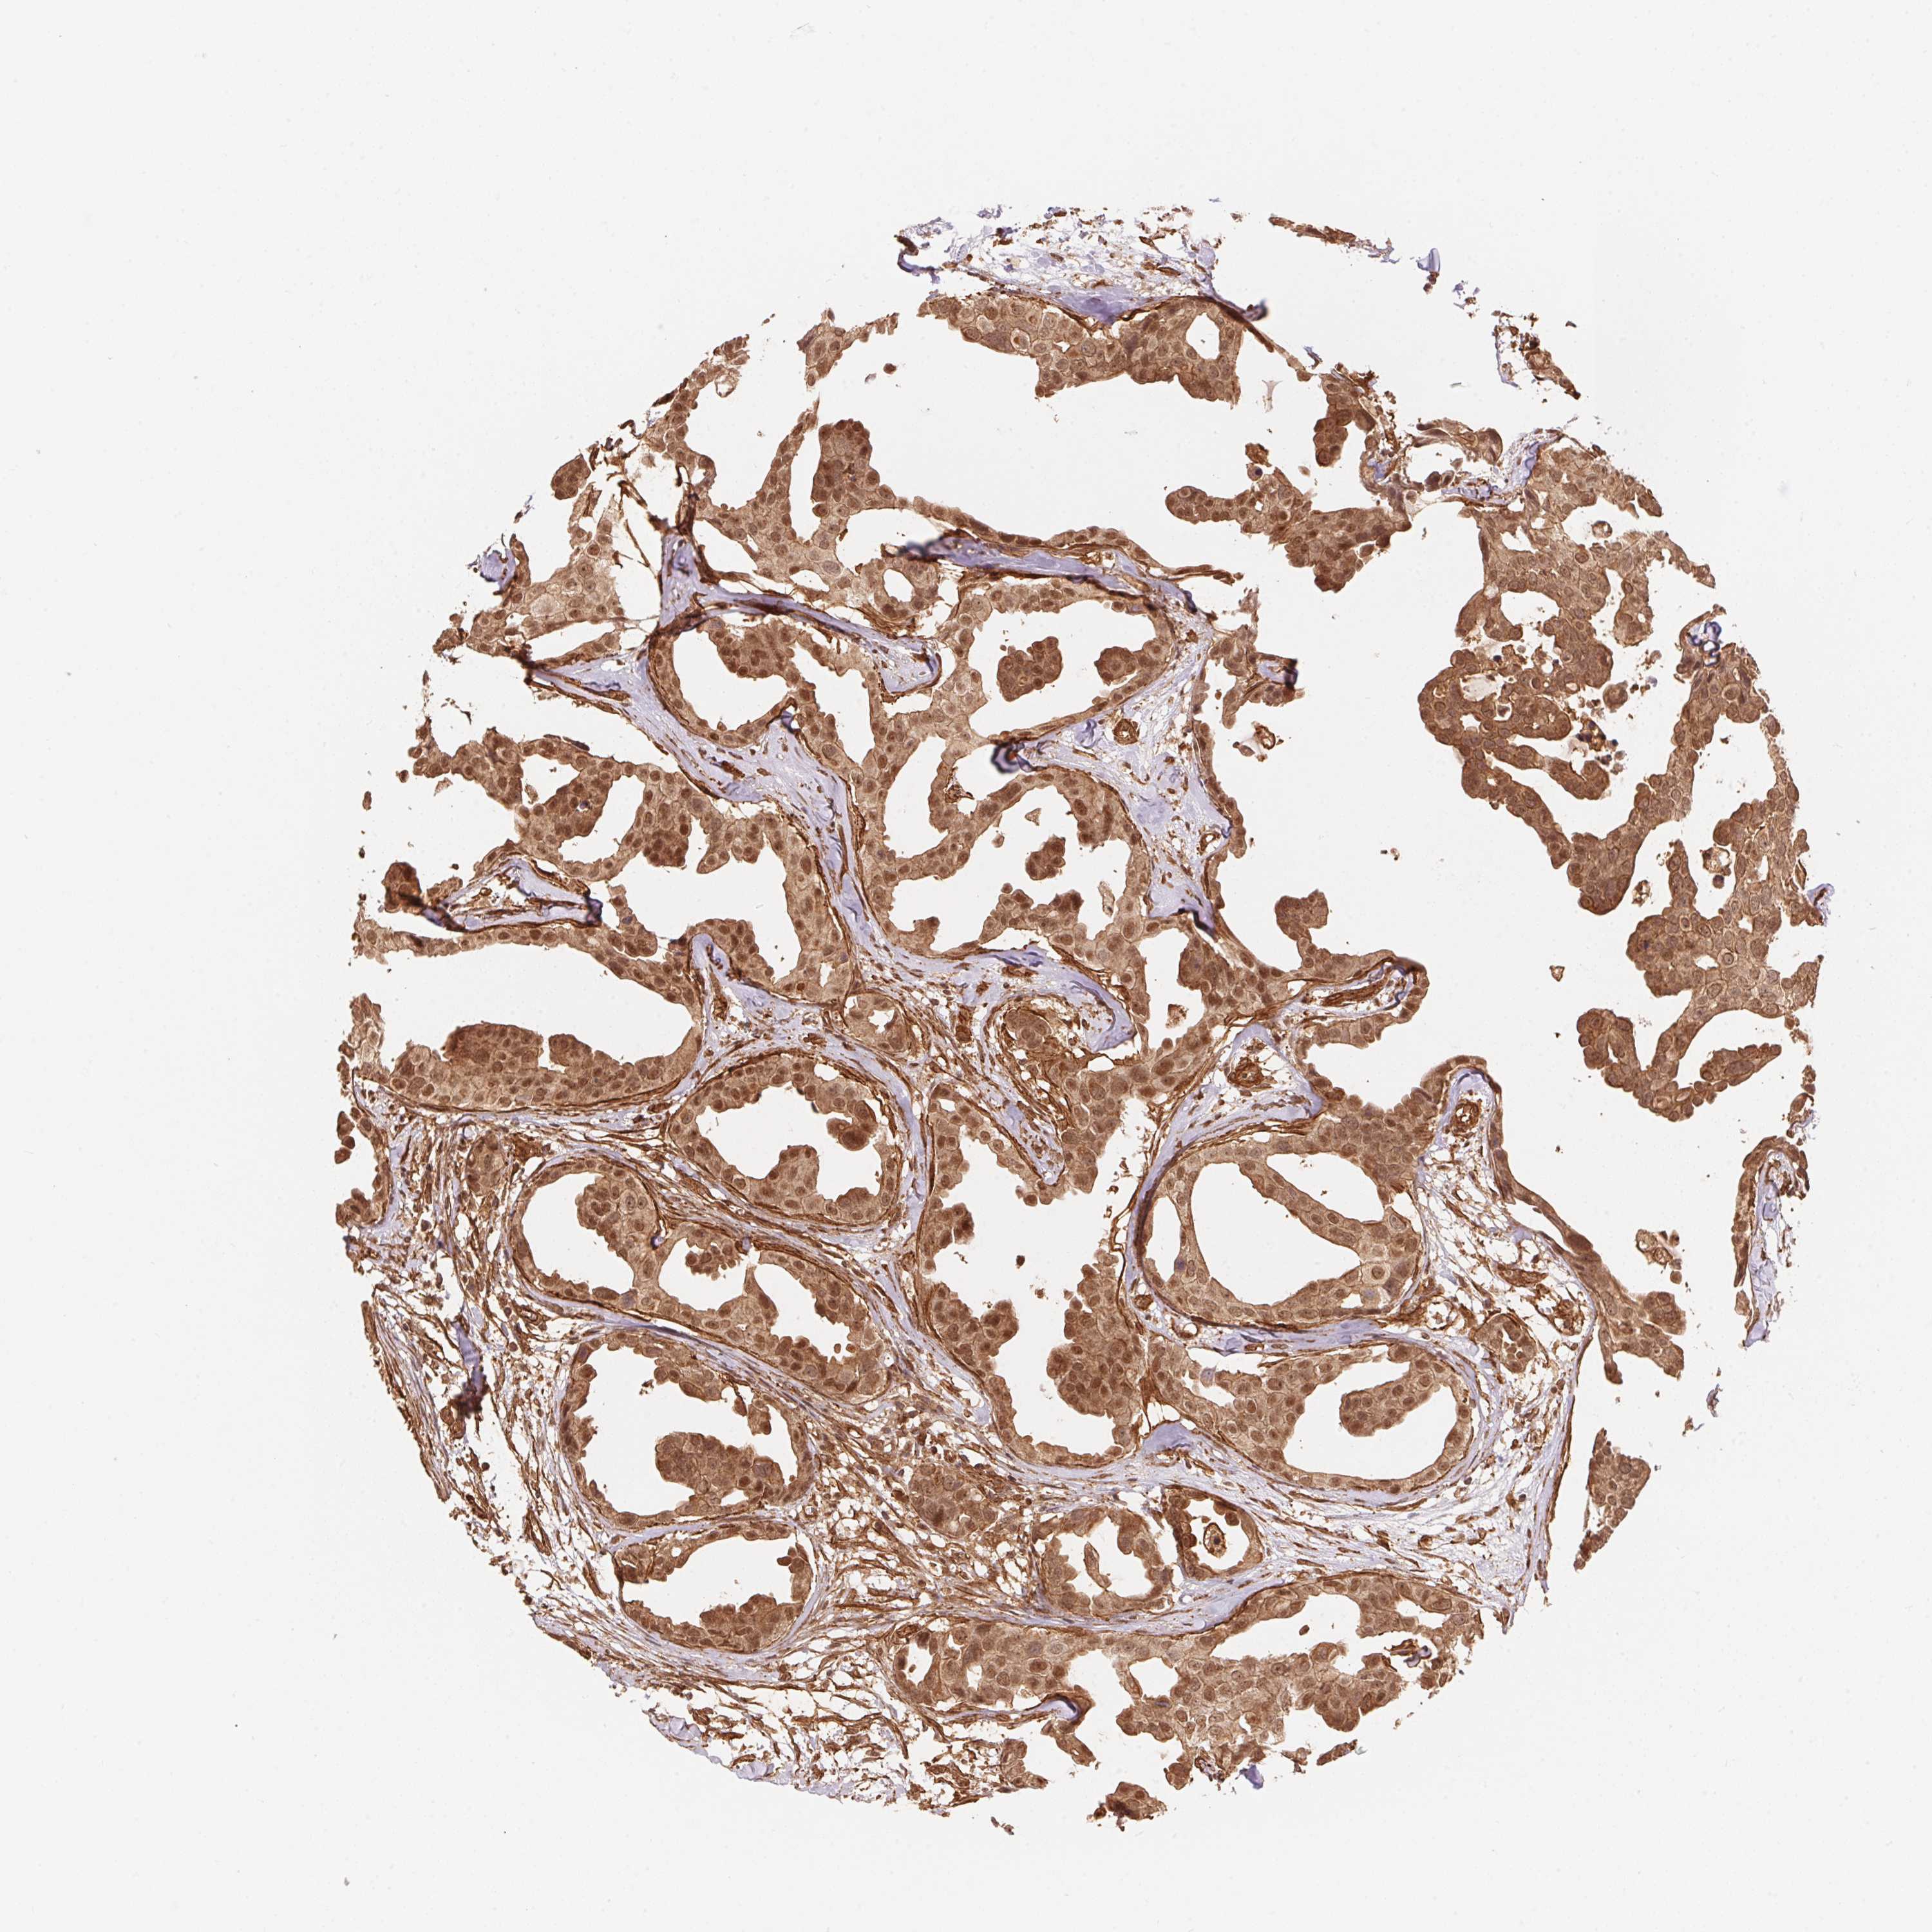

CANCER BREAST CANCER Show tissue menu

BRCA TCGA BRCA VALIDATION PROTEIN EXPRESSION